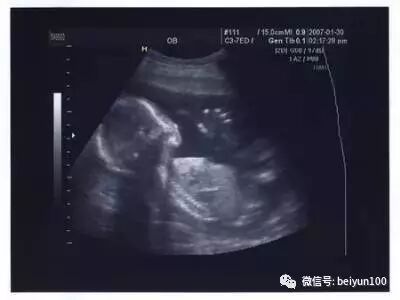

医学研究发现,男女婴儿在子宫内都可能产生手淫的举措。超声波图像曾抓拍到男婴的勃起图片,不过由于生殖器官差异的原因,只有男性能在X光片上看出来。